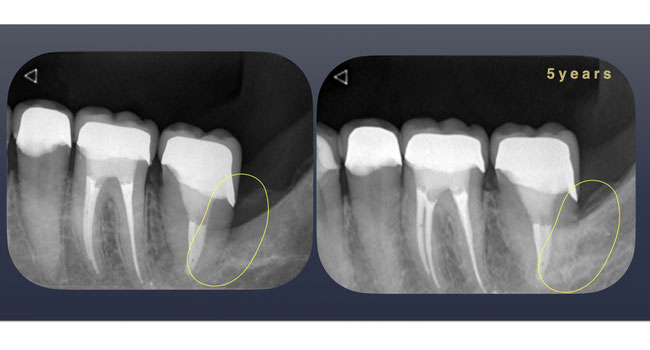

口腔内は奥歯で噛める箇所がほとんどない状態で受診され口の中全体を長期にわたって治療した。そのうちの1箇所であるがインプラントや入れ歯でなく自身の歯で噛めるようになった。移植した歯の後方に骨が回復しているのが確認できる。

被せ物装着時と移植5年後のレントゲン写真を比較すると○部に骨が再生されているのが確認できる。インプラント治療ではこのように骨を作ることは不可能である。「歯根膜」を有する自身の歯を利用した移植治療ならではである。